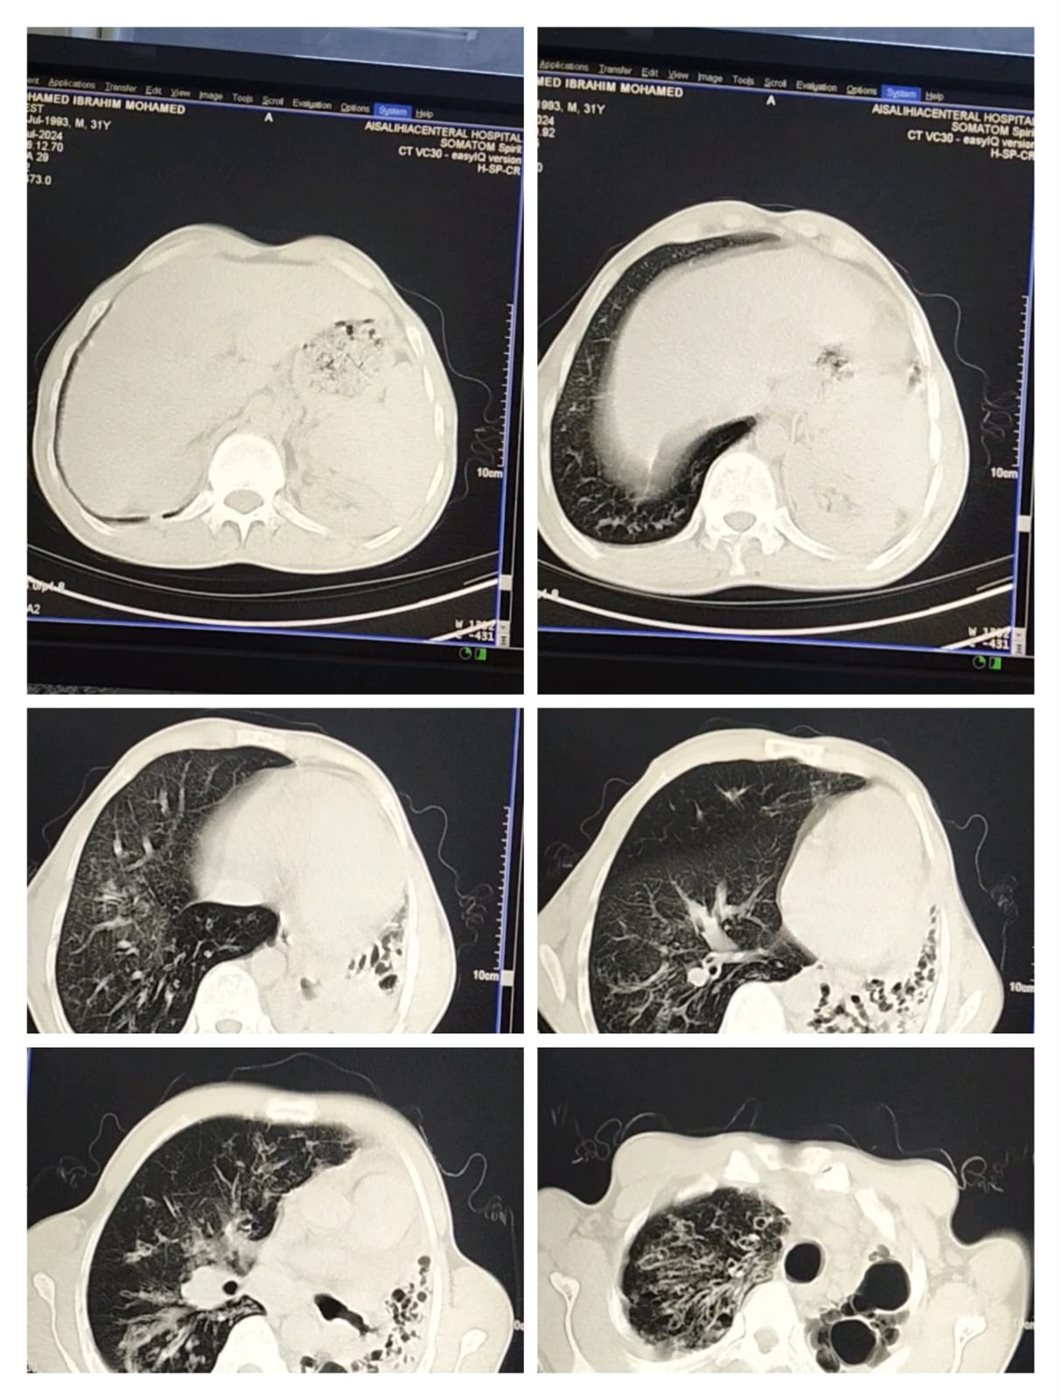

وأكمل محمد إبراهيم محمد سلطان، مريض التليف الرئوي بالشرقية: الدكاترة قالولي لازم تفضل على الأكسجين وممنوع التعرض لـ الروائح والإجهاد، وفعلًا وقفت شغل من سنة 2020، مضيفًا: الرئة الشمال توقفت عن العمل ومتليفة بشكل كامل، والرئة اليمين شغالة بنسبة 30%، أنا كنت شغال استورجي موبيليا وكان عندي ورشة، والآن عايش على معاش والدي، لإني أجلس على مولد أكسجين بالمنزل، ومحتاج لعملية زراعة رئتين.